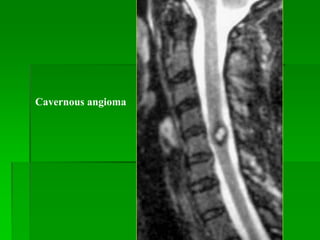

Cavernous angioma

HEMANGIOBLASTOMA

 U hiếm gặp.

 Thường gặp nang lành tính trong tủy kèm nốt mạch máu.

 Triệu chứng khởi đầu từ 30-40 tuổi, 1/3 trường hợp có hội

chứng Von Hippel-Lindau.

 80% u trong tủy hay phối hợp trong tủy/trong màng cứng-

ngoài tủy.

 50% ở ngực, 40% ở cổ.

MRI:

- T1W: đồng tín hiệu tủy sống , T2W: tăng tín hiệu.

- Thường có flow void.